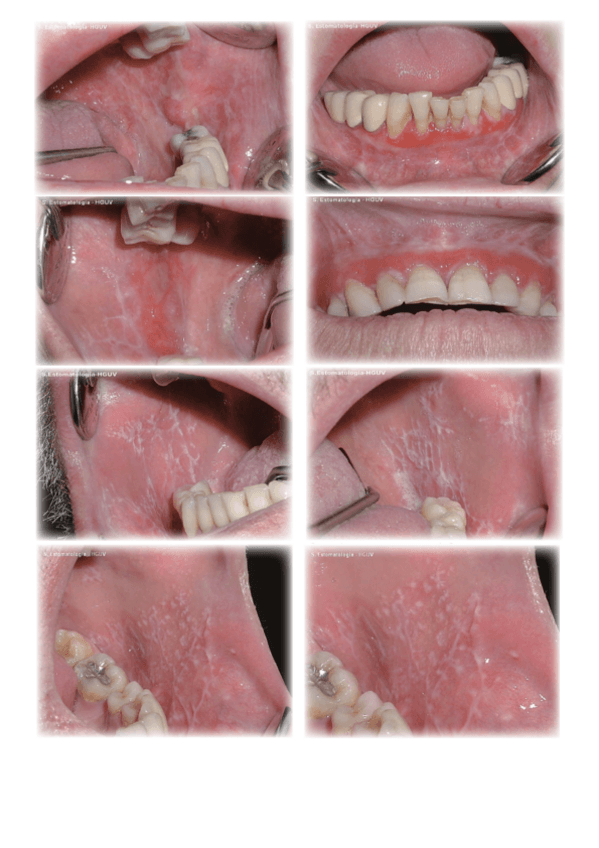

Imagenes-Practicas.pdf